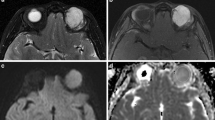

Tables 1 and 2 describe the frequency distribution of nonenhanced MR imaging features (Table 1) and static and DCE MR imaging features (Table 2), correlation of these features with pathological diagnosis (benign or malignant tumors) for observer 1, as well as interobserver agreement between observers 1 and 2. For both observers, there was significant difference between the benign group and the malignant group in the location, shape, and margin of the mass, homogeneity on T1- and T2-weighted imaging, signal intensity on T2-weighted imaging, pattern of enhancement, and type of time–intensity curve (TIC) (P < 0.05) (Figs. 1, 2, 3, and 4). For both observers, tumor location including extraconal space and anterior orbit preseptal space, irregular shape, ill-defined margin, molding around orbital structures, a homogeneous mass on T1- and T2-weighted imaging, isointensity relative to extraocular muscle on T2-weighted imaging, homogeneous enhancement, and washout-type TIC were correlated (P < 0.05) with the diagnosis of malignancy (Figs. 1, 2, and 3).

Transverse MR images in a 79-year-old man demonstrated a well-circumscribed mass molding around the globe in the left preseptal space (arrowhead) and extraconal space (arrow). a T1-weighted image (400/15) showed a homogeneously isointense mass relative to extraocular muscle. b T2-weighted image (3,000/120) showed a homogeneously isointense mass relative to extraocular muscle. c Static contrast-enhanced MR image (400/15) with fat suppression showed mildly homogeneous enhancement of the mass. d Time–intensity curve for this patient was characterized as a washout curve. Pathologic examination revealed a non-Hodgkin’s lymphoma